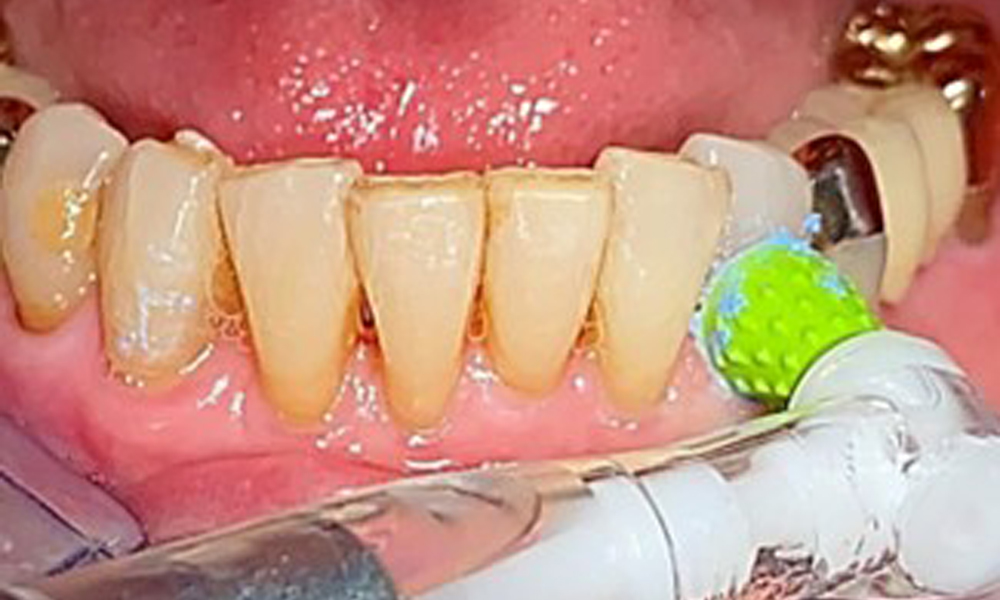

Специално за телескопичните протези се препоръчва еднократна четка (фиг. 8), а пациентът трябва да бъде посъветван за подходящия размер на интерденталната четка (фиг. 9). Пациентът изпълнява тези препоръки за интраорална хигиена у дома в продължение на много години и беше насърчен да продължи по време на професионалната профилактична среща с денталния лекар.

Трябва да се използва система за въздушно полиране с нискоабразивна пудра за отстраняване на биофилма от ръбовете на възстановяването, интерденталните зони и повърхностите на импланта (фиг. 12). Селективното полиране (фиг. 13) трябва да се използва за изглаждане на всички по-малко чувствителни зони, тъй като това намалява повторното прикрепване на бактерии (9).